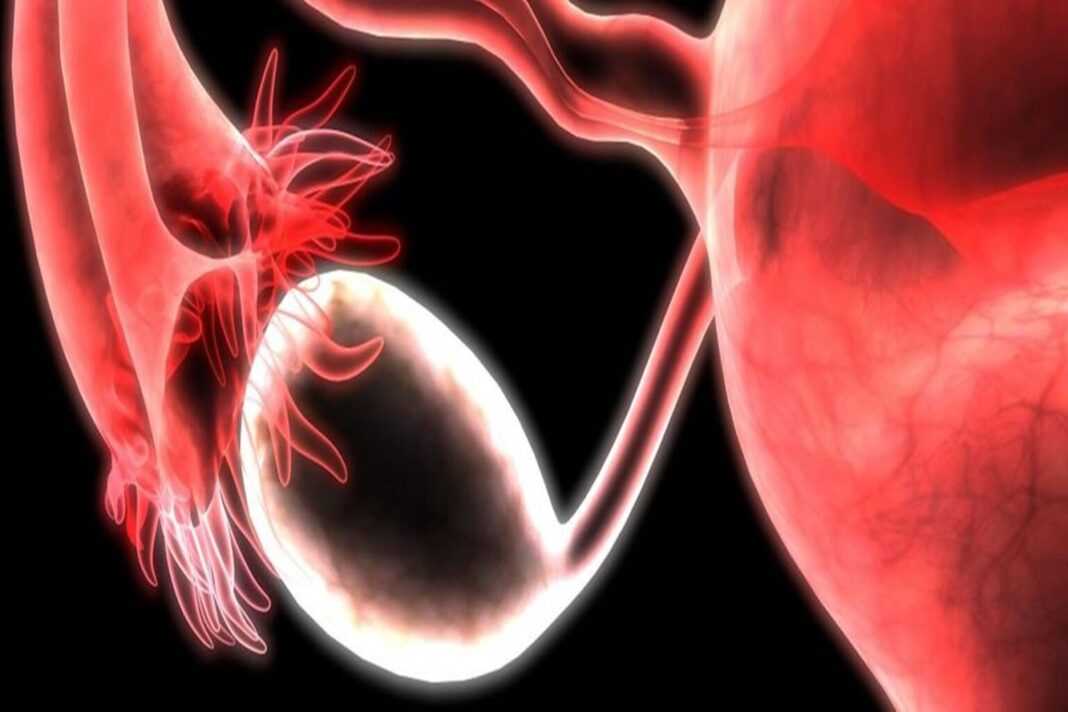

Η ωορρηξία συμβαίνει όταν μία από τις ωοθήκες απελευθερώνει ένα ώριμο ωάριο. Αυτή είναι η στιγμή που το σώμα είναι έτοιμο να λάβει σπέρμα για γονιμοποίηση. Εάν δεν υπάρξει γονιμοποίηση, το αυγό αποσυντίθεται στην επένδυση της μήτρας. Στη συνέχεια, το σώμα θα ρίξει τα υπολείμματα κατά τη μηνιαία περίοδο ενός ατόμου.

Η ωορρηξία διαρκεί οπουδήποτε από 12-24 ώρες. Αφού η ωοθήκη απελευθερώσει ένα ωάριο, επιβιώνει για περίπου 24 ώρες πριν πεθάνει, εκτός εάν το σπέρμα γονιμοποιήσει.